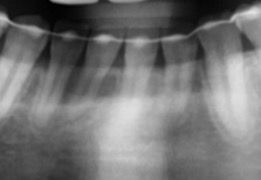

교정 끝난 바로 직후 엑스레이에 뿌리염증이 보이는데 지금은 또 없습니다

교정 끝난 직후에 파노라마 사진을 찍었는데 그 당시에는 뿌리에 염증있는 것 처럼 보였는데 5년정도 지난 지금 파노라마에는 또 안보입니다. 혹시 생겼던 염증이 사라진건가요? 가끔씩 해당 치아가 시리긴 했는데 치과에서는 잇몸이 얇아서 그렇다고 하시곤 염증은 없다 하셨거든요 원인이 뭔가요? 그리고 뿌리염증처럼 보이는게 왜 사라진걸까요? 교정 직후라서 잇몸이 안좋아서 그런가요?

• 1번 째 사진